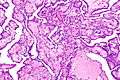

Histology

Cancer cells have distinguishing histological features visible under the microscope. The nucleus is often large and irregular, and the cytoplasm may also display abnormalities.[3]

Nucleus

The shape, size, protein composition, and texture of the nucleus are often altered in malignant cells. The nucleus may acquire grooves, folds or indentations, chromatin may aggregate or disperse, and the nucleolus can become enlarged. In normal cells, the nucleus is often round or ellipsoid in shape, but in cancer cells the outline is often irregular. Different combinations of abnormalities are characteristic of different cancer types, to the extent that nuclear appearance can be used as a marker in cancer diagnostics and staging.[4]